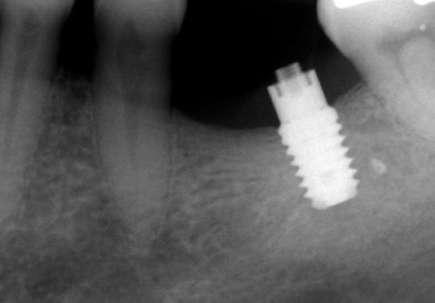

Figuras 3-6. Imágenes de un caso de prótesis atornillada en molar unitario inferior. Vemos el estado de los tejidos blandos gingivales tras la segunda fase y colocación del transepitelial unitario y la radiografía. En las imágenes inferiores (5 y 6) observamos el caso a los 4 años y 10 años de seguimiento, con estabilidad completa de los tejidos óseos peri-implantarios.

Figuras 7-10. En las dos imágenes superiores (7 y 8) observamos la realización de la prótesis cementada mediante un bioplilar fresado a la altura gingival con la radiografía antes del cementado de la corona. En las imágenes inferiores (9 y 10) vemos la prótesis a los 7 años de seguimiento y a los 9 años transformada en una prótesis atornillada al perderse la pieza anterior al implante y realizarse un puente con el nuevo implante. En este caso, el nivel óseo permanece estable con el paso del tiempo.